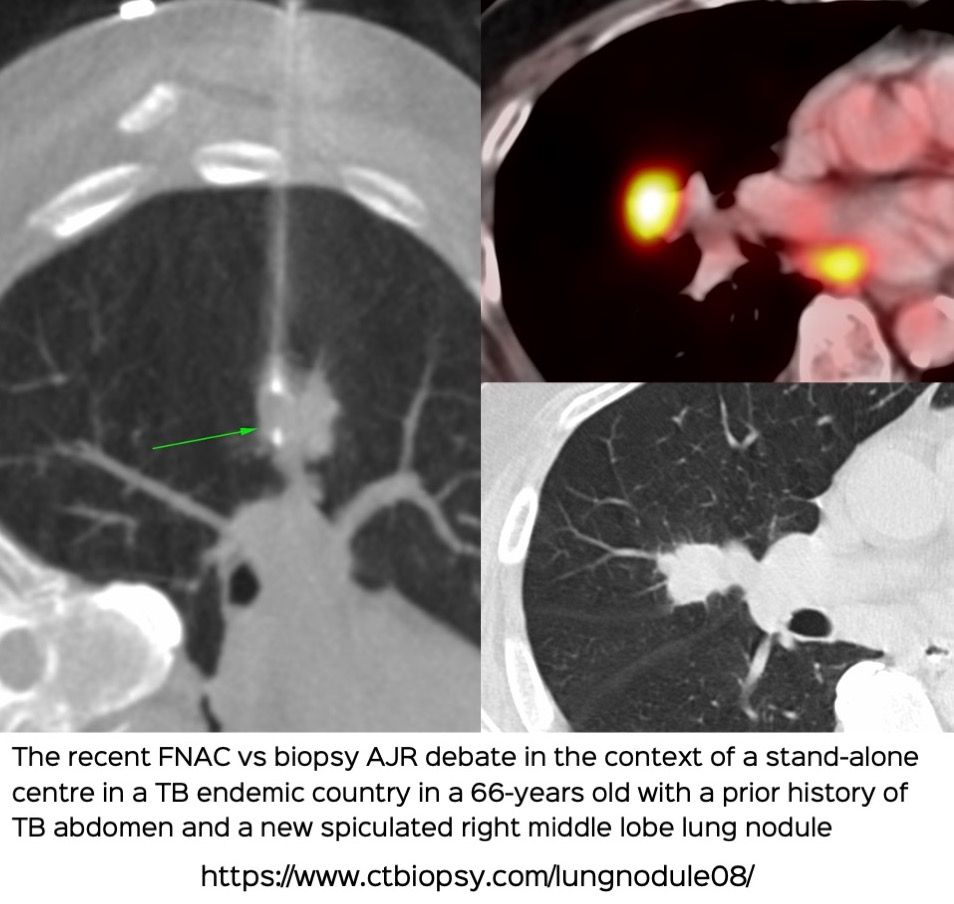

Case 67: Lung Nodule - FNAC vs Biopsy – The Recent Debate in the AJR in the Context of a Deep Lung Nodule Biopsy

Bhavin Jankharia - 19 November 2021